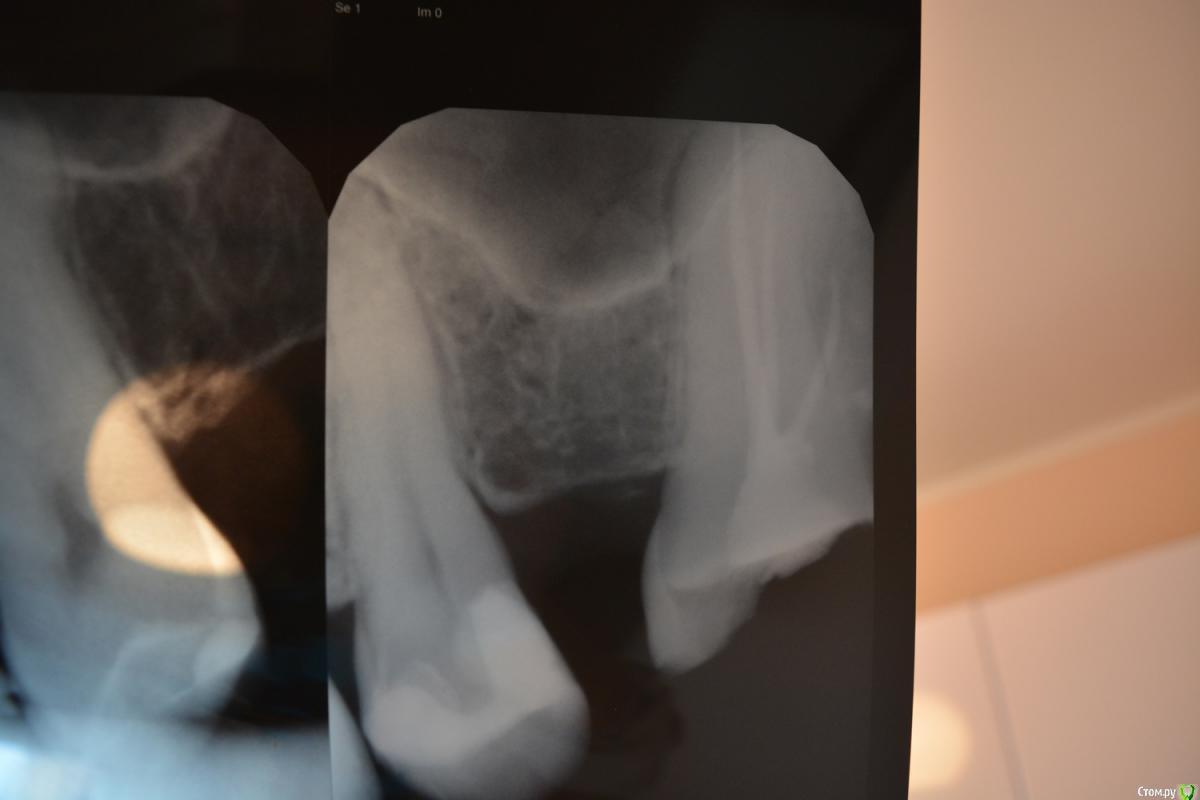

kozloff Опубликовано 3 сентября, 2015 Поделиться Опубликовано 3 сентября, 2015 Очень много нюансов, мы не видим всей картины, в частности прикуса и степени стираемости имеющихся зубов, поэтому если хотите еще одно мнение - вперед на очную консультацию или выкладывайте панорамный снимок, фотографии, диагностические модели. Вам уже обрисовали годный план лечения, остальное - компромиссы. Решать Вам.http://forum.stom.ru/topic/2813-obiazatelno-k-prochteniiu/ Ссылка на комментарий